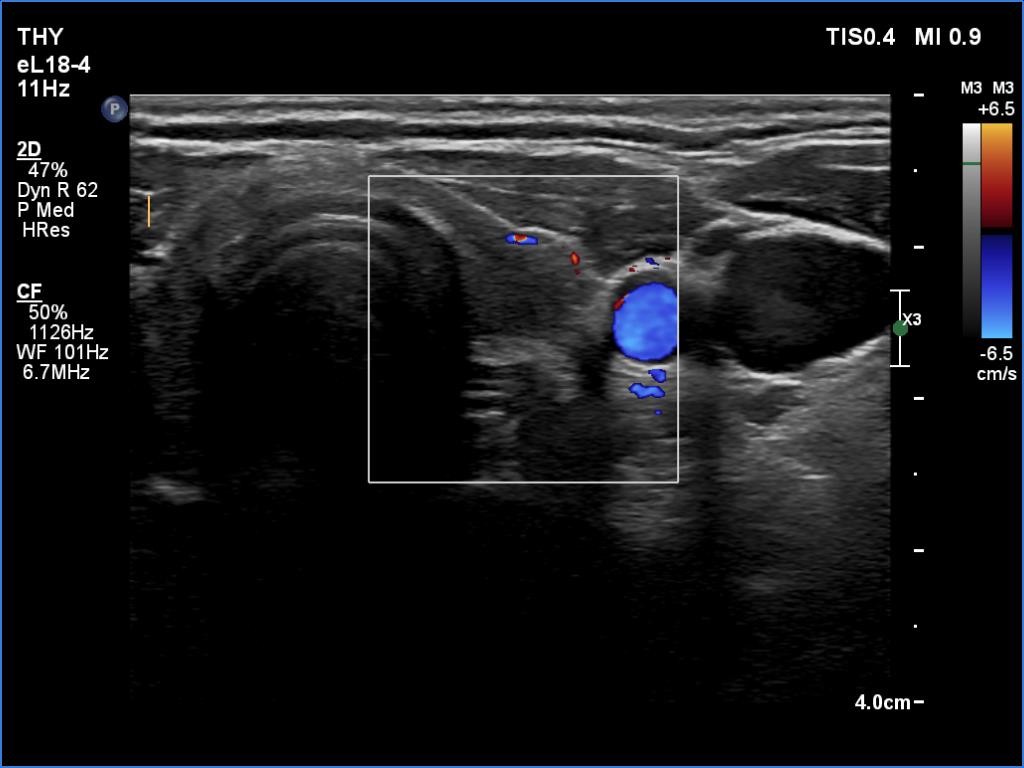

Second examination a year later (ultrasonographic picture 7)

Left lobe, transverse scan, color Doppler mode. The vascularization is decreased.